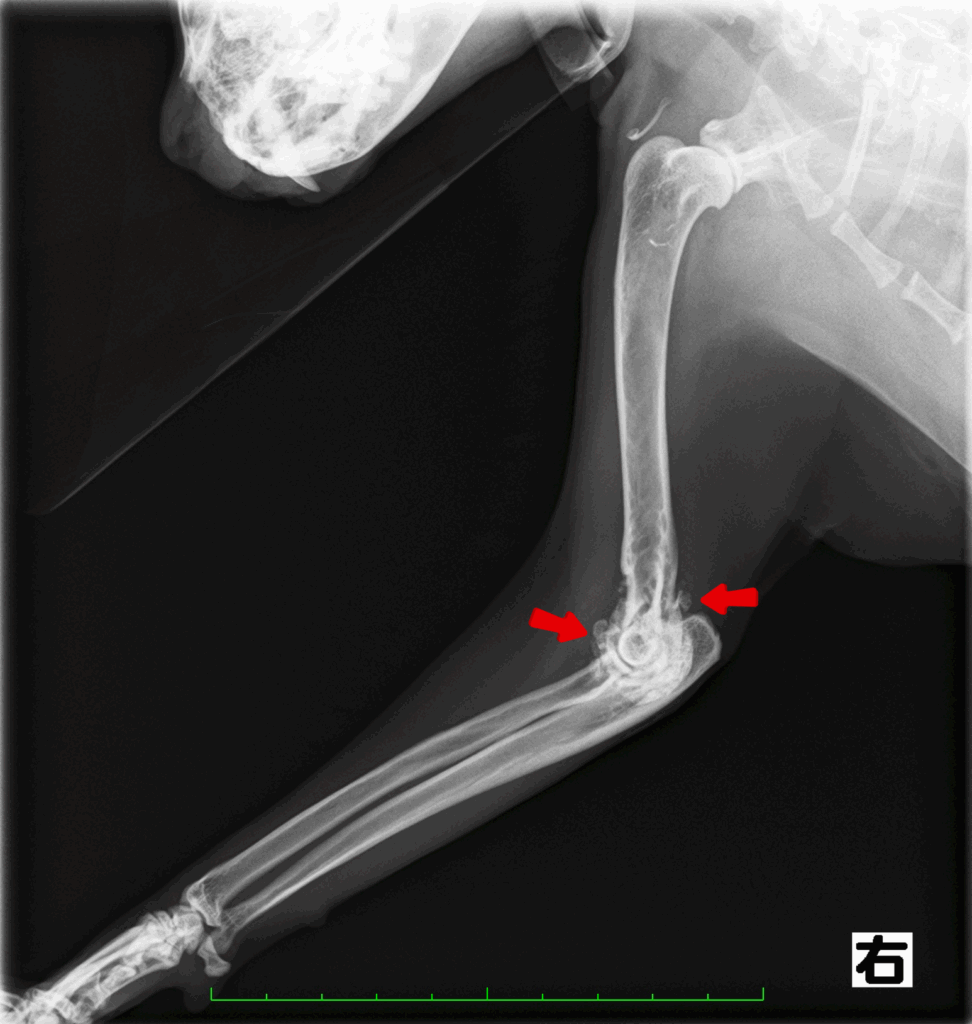

診断するにはレントゲン検査です。

関節にできた骨棘や石灰化病変を確認することで診断していきます。

特に肘関節と股関節の異常が多く認められます。